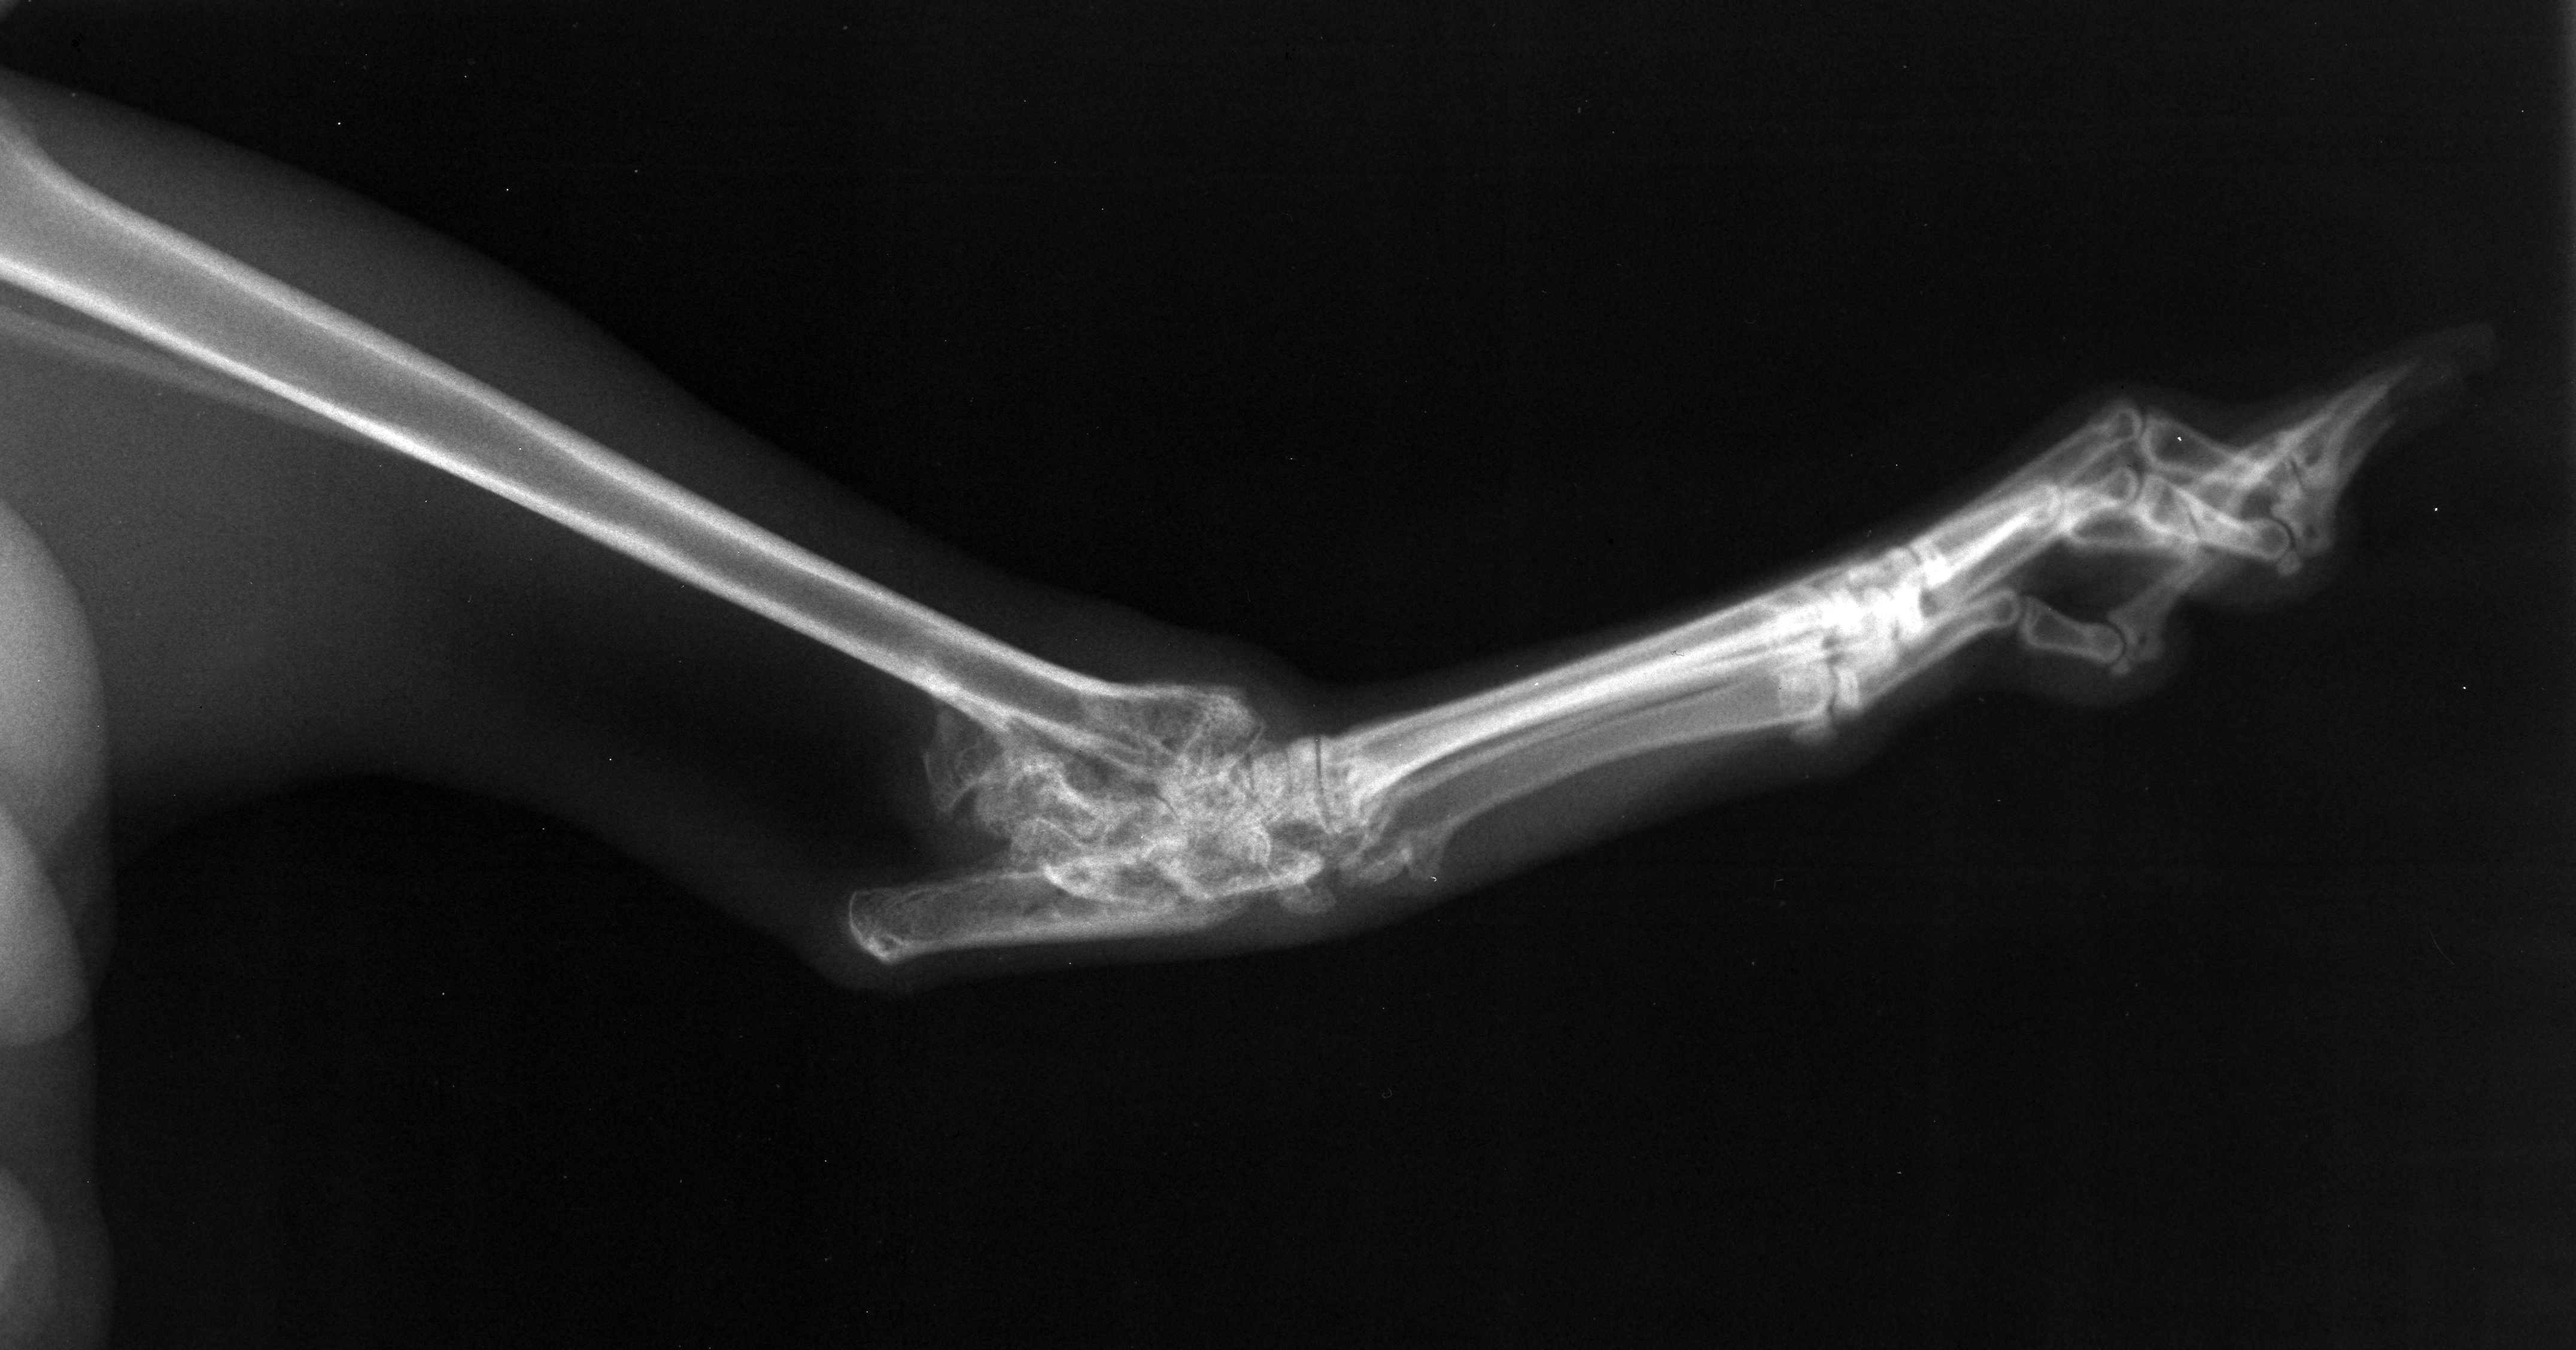

Jack's hock

Jack with fractured leg

Jack lateral hock

Radiograph